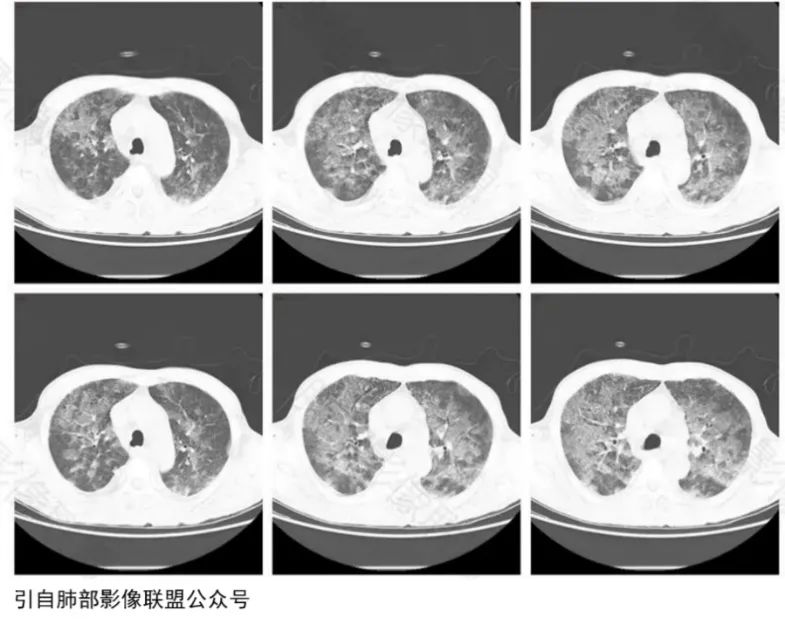

17岁女性患者,因车祸伤致右侧胫腓骨骨折,4天后患者出现咳嗽、气紧及咯血,胸部CT(图3)示双肺散在磨玻璃样密度影及斑片、结节影,予以吸氧、糖皮质激素治疗2周后复查胸部CT示双肺病灶基本吸收。结合患者长骨骨折病史以及双肺暴风雪样改变,提示脂肪栓塞可能。

图3脂肪栓塞综合征